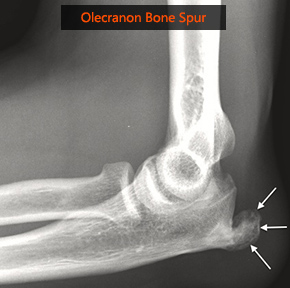

Bone Spurs Of The Elbow Arm Docs

Pdf Surgical Management Of Symptomatic Olecranon Traction Spurs